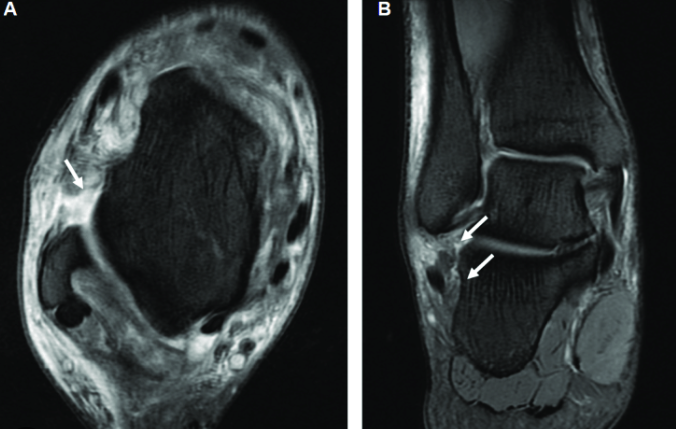

초음파·MRI: 인대 손상 및 파열 상태 정밀 확인.

♼ 손상 정도 구분

2도: 인대가 부분적으로 파열됨

3도: 인대가 완전히 끊어진 상태(완전 파열)